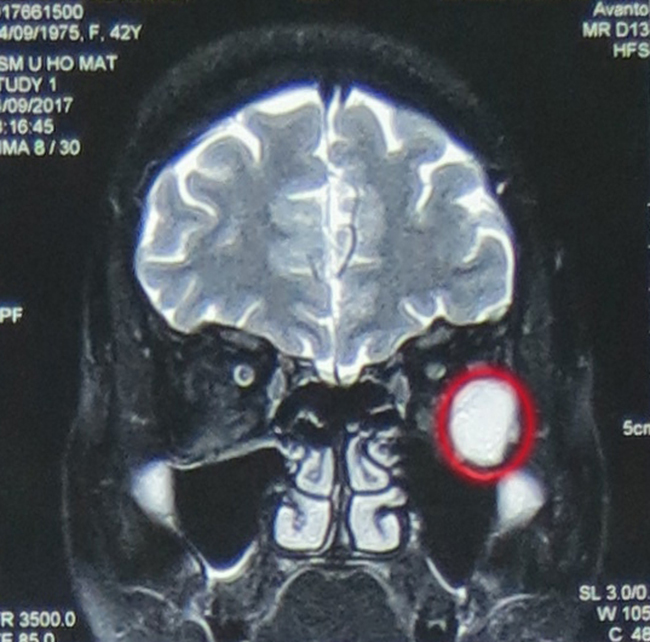

Hình ảnh phim chụp cho thấy, bệnh nhân N.T.M.T có khối u hốc mắt trái, kích thước 21x17x23mm |

Chị quyết định tới bệnh viện Việt Đức để điều trị và được chẩn đoán u hốc mắt trái, kích thước 21x17x23mm, khối gây đè đẩy các cơ vận nhãn, nhãn cầu và dây thần kinh thị giác vào trong làm lồi nhãn cầu trái độ I, các bác sỹ khoa Phẫu thuật Thần kinh I đã hội chẩn và tiến hành phẫu thuật nội soi cắt u hốc mắt qua đường mũi.